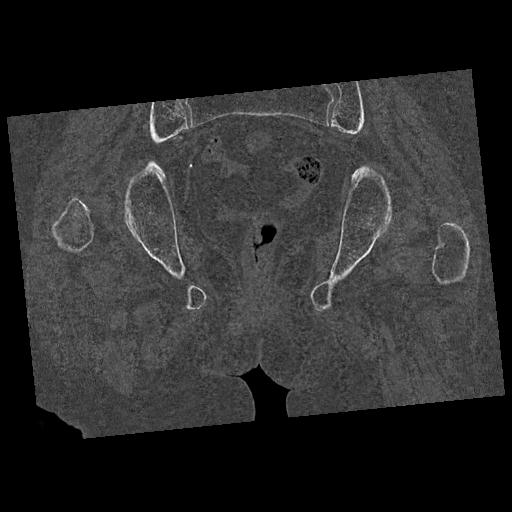

102803 1/12(キウスなし) 1/27 左下腿 4R 30歳女性 左脛骨軸内釘